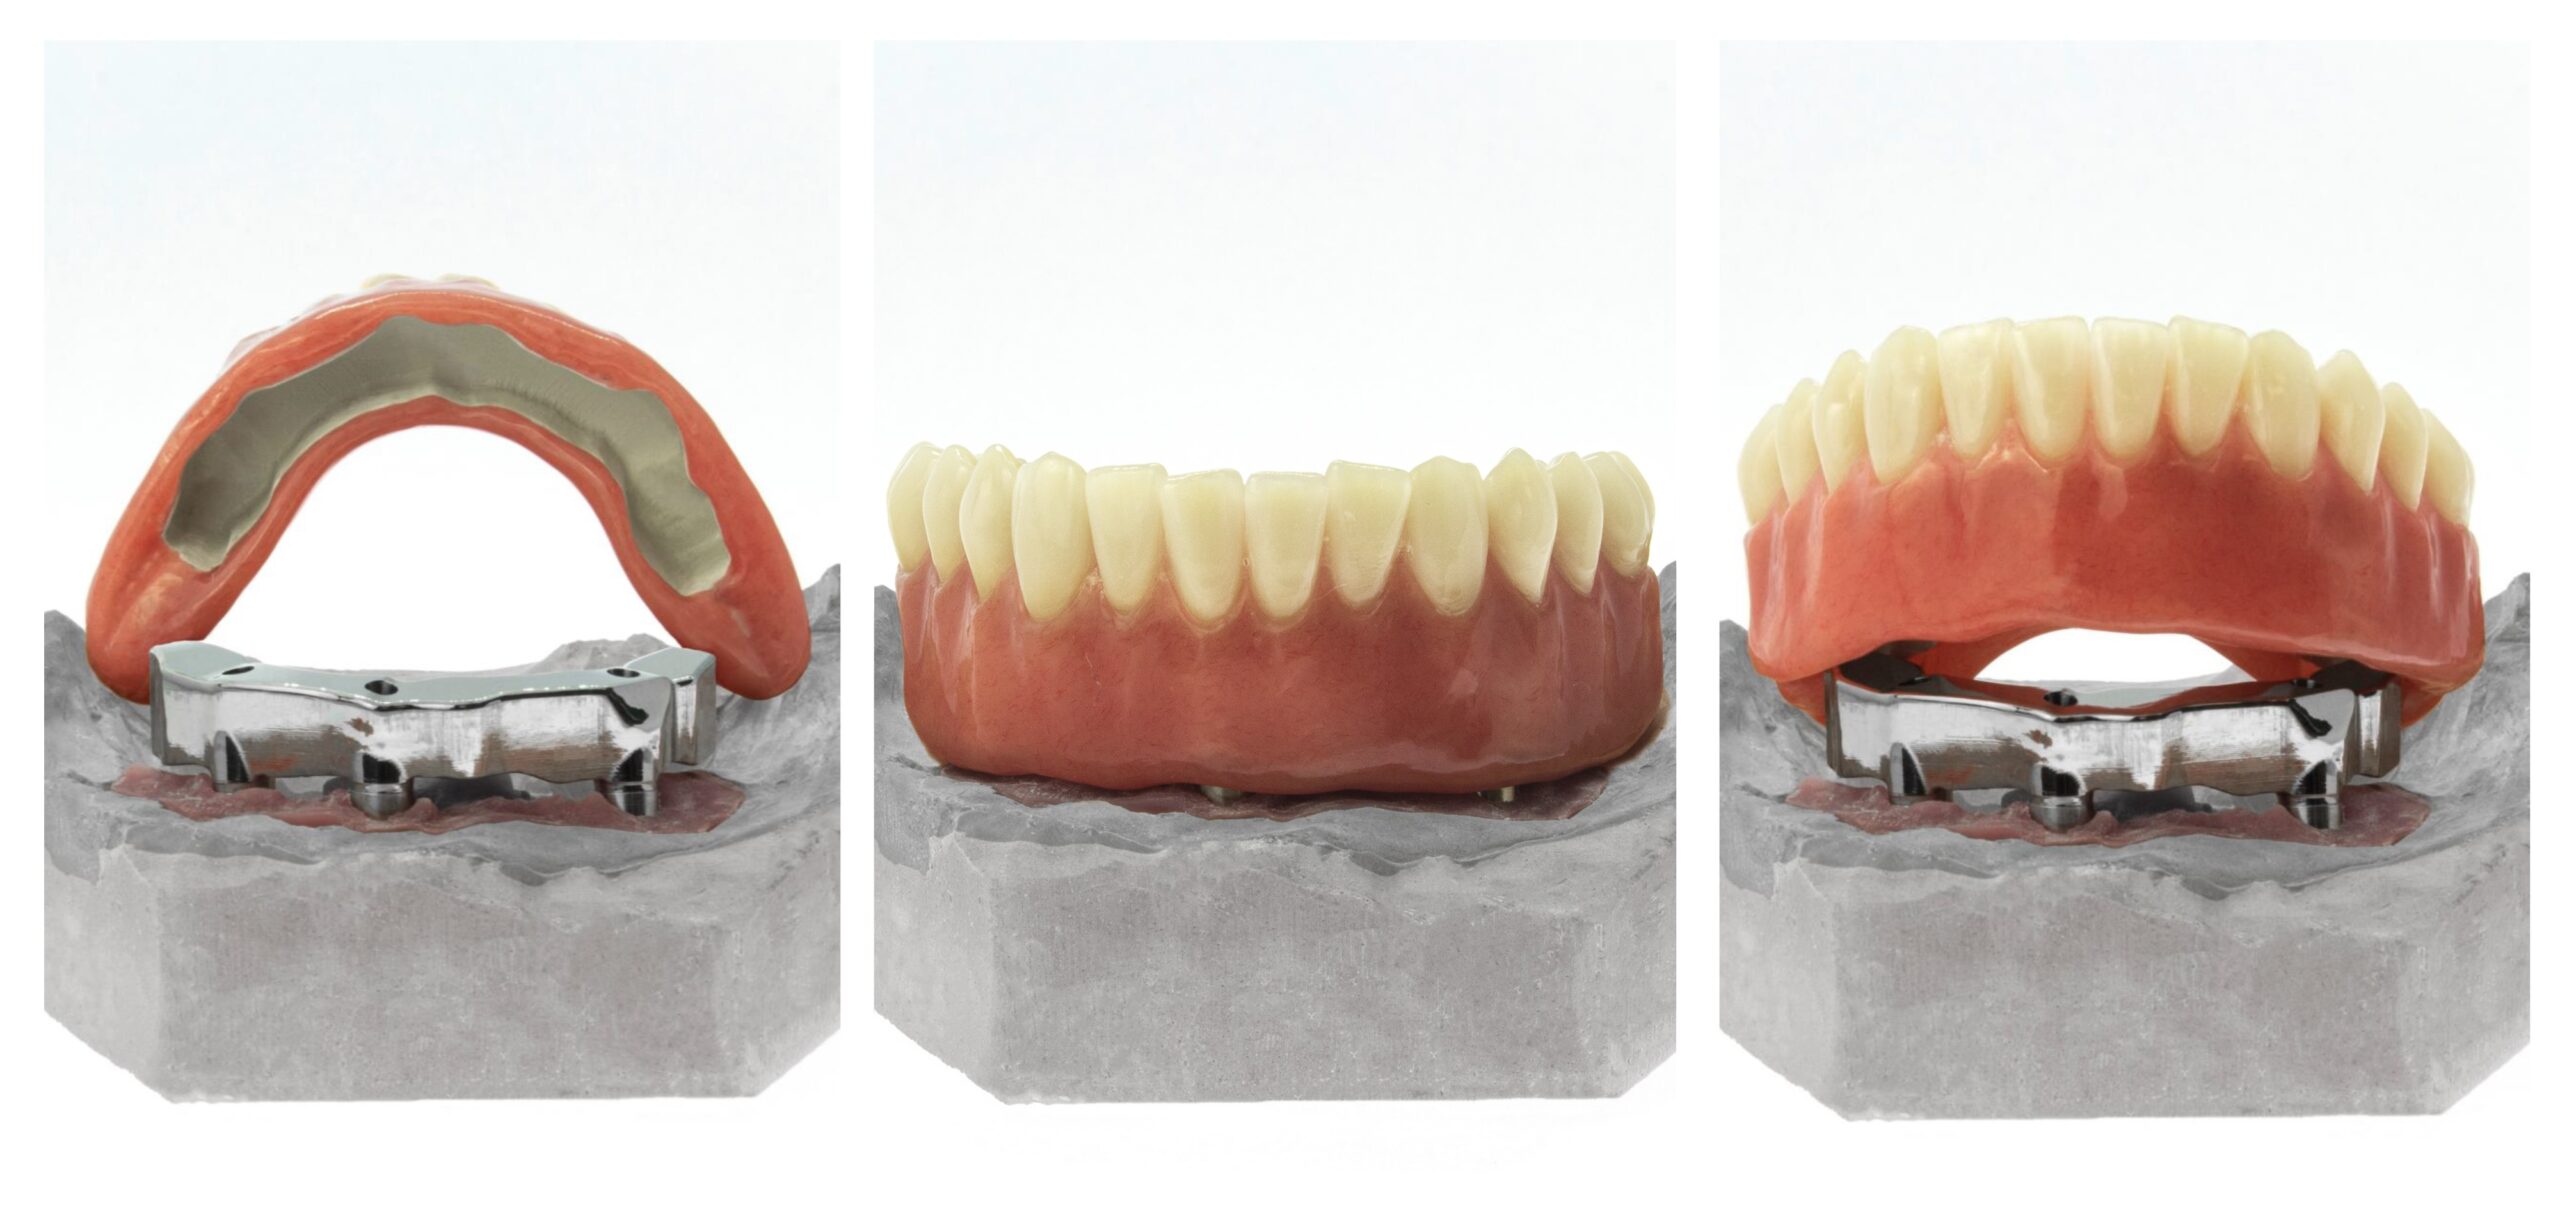

Nuestras restauraciones telescópicas son la solución perfecta para aquellos casos que precisan de una prótesis removible con un elemento fijo para brindarles la estabilidad de una prótesis fija.

Estos trabajos se componen de una barra primaria fabricada en Titanio que se atornilla a los implantes del paciente y sobre la que se apoya una estructura secundaria fabricada en PEEK. Esta supraestructura que se adapta por fricción a la barra, tiene una gran resiliencia que le permite no perder su forma para mantener su capacidad retentiva y amortiguar las fuerzas oclusales.

El PEEK tiene, además, unas propiedades químicas que lo convierten en el material idóneo para unirse con la resina de encías, lo que disminuye la probabilidad de sufrir roturas en la prótesis.